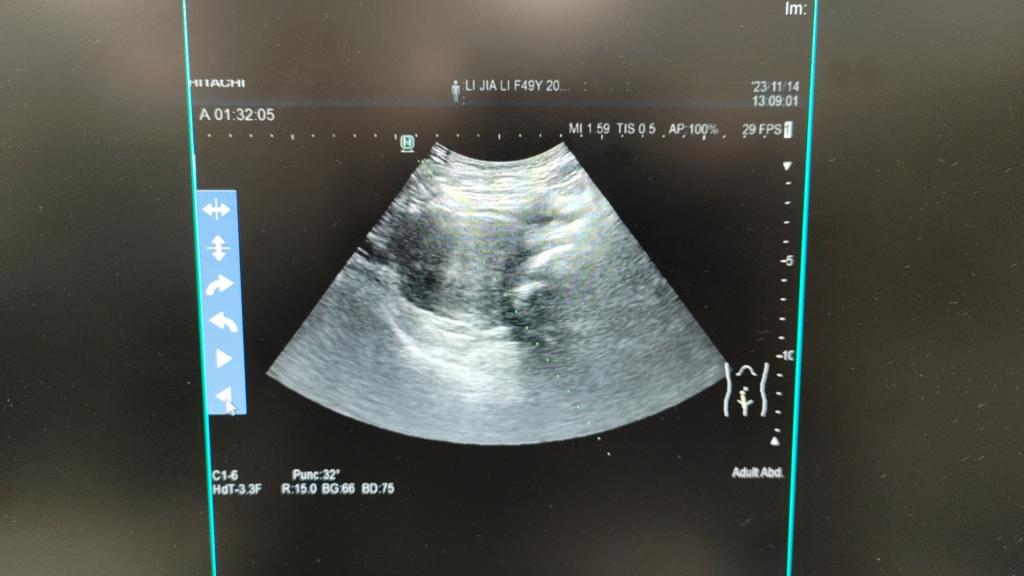

2023年11月14日,我院妇科二病区主任梁月秀带领团队,在麻醉科覃福兴医师、超声科专家利青及麻海智医师的协作下,在全身麻醉下为患者成功施行了超声引导下人工腹水+超声引导下宫颈病灶微波消融术+宫颈病灶穿刺活检术+宫颈病灶穿刺注射聚桂醇硬化治疗。术中,我院妇科二病区梁月秀主任团队运用娴熟的操作技术,在超声引导下合理选择手术入路,将微波消融针直接穿刺到病变部位,对患者病灶进行了多点位消融灭活,由消融针释放的热磁场可以使周围的分子高速旋转运动并摩擦升温,从而使消融区组织发生不可逆凝固性坏死,使病灶缩小或逐渐消失,达到治疗的目的。消融后,梁月秀主任团队再次用超声造影即刻评估消融灶无血供区达到预期,准确迅速地完成了此例次全子宫切除术后宫颈病灶微波消融术。

消融后,我院妇科二病区梁月秀主任团队再次用超声造影即刻评估消融灶无血供区达到预期,准确迅速地完成此例次全子宫切除术后宫颈病灶微波消融术